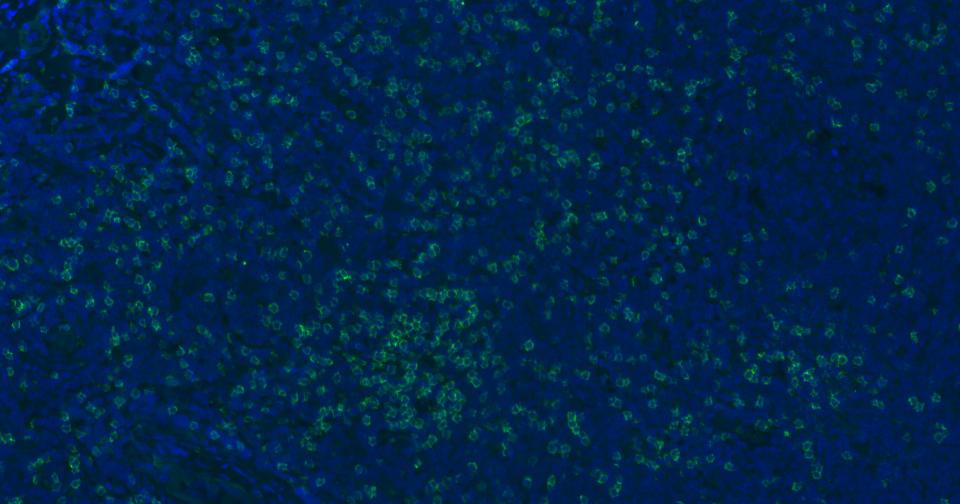

Paraformaldehyde-fixed, paraffin embedded Human Tonsil; Antigen retrieval by boiling in sodium citrate buffer (pH6.0) for 15 min; Antibody incubation with CD8 Polyclonal Antibody, Unconjugated (bsm-61078R) at 1:200 overnight at 4°C. Followed by conjugated Goat Anti-Rabbit IgG antibody (green, bs-0295G-BF488), DAPI (blue, C02-04002) was used to stain the cell nuclei.